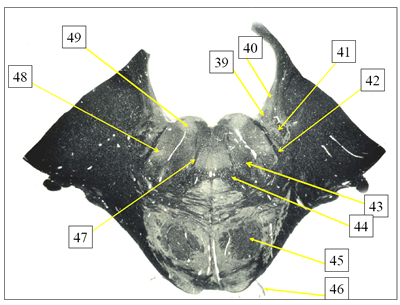

Figure 6

60. Structure #39

61. Structure #40

62. Structure #41

63. Structure #42

64. Structure #43

65. Structure #44

66. Structure #45

67. Structure #46

68. Structure #47

69. Structure #48

70. Structure #49

1. Abducens nerve

2. Abducens nerve root

3. Abducens nucleus

4. Central tegmental tract

5. Corticofugal fibers

6. Facial nerve root

7. Facial nucleus

8. Inferior vestibular nucleus

9. Inferior cerebellar peduncle

10. Lateral vestibular nucleus

11. Medial lemniscus

12. Medial vestibular nucleus

13. Solitary nucleus

14. Spinal trigeminal nucleus

15. Superior vestibular nucleus

16. Ventral cochlear nucleus